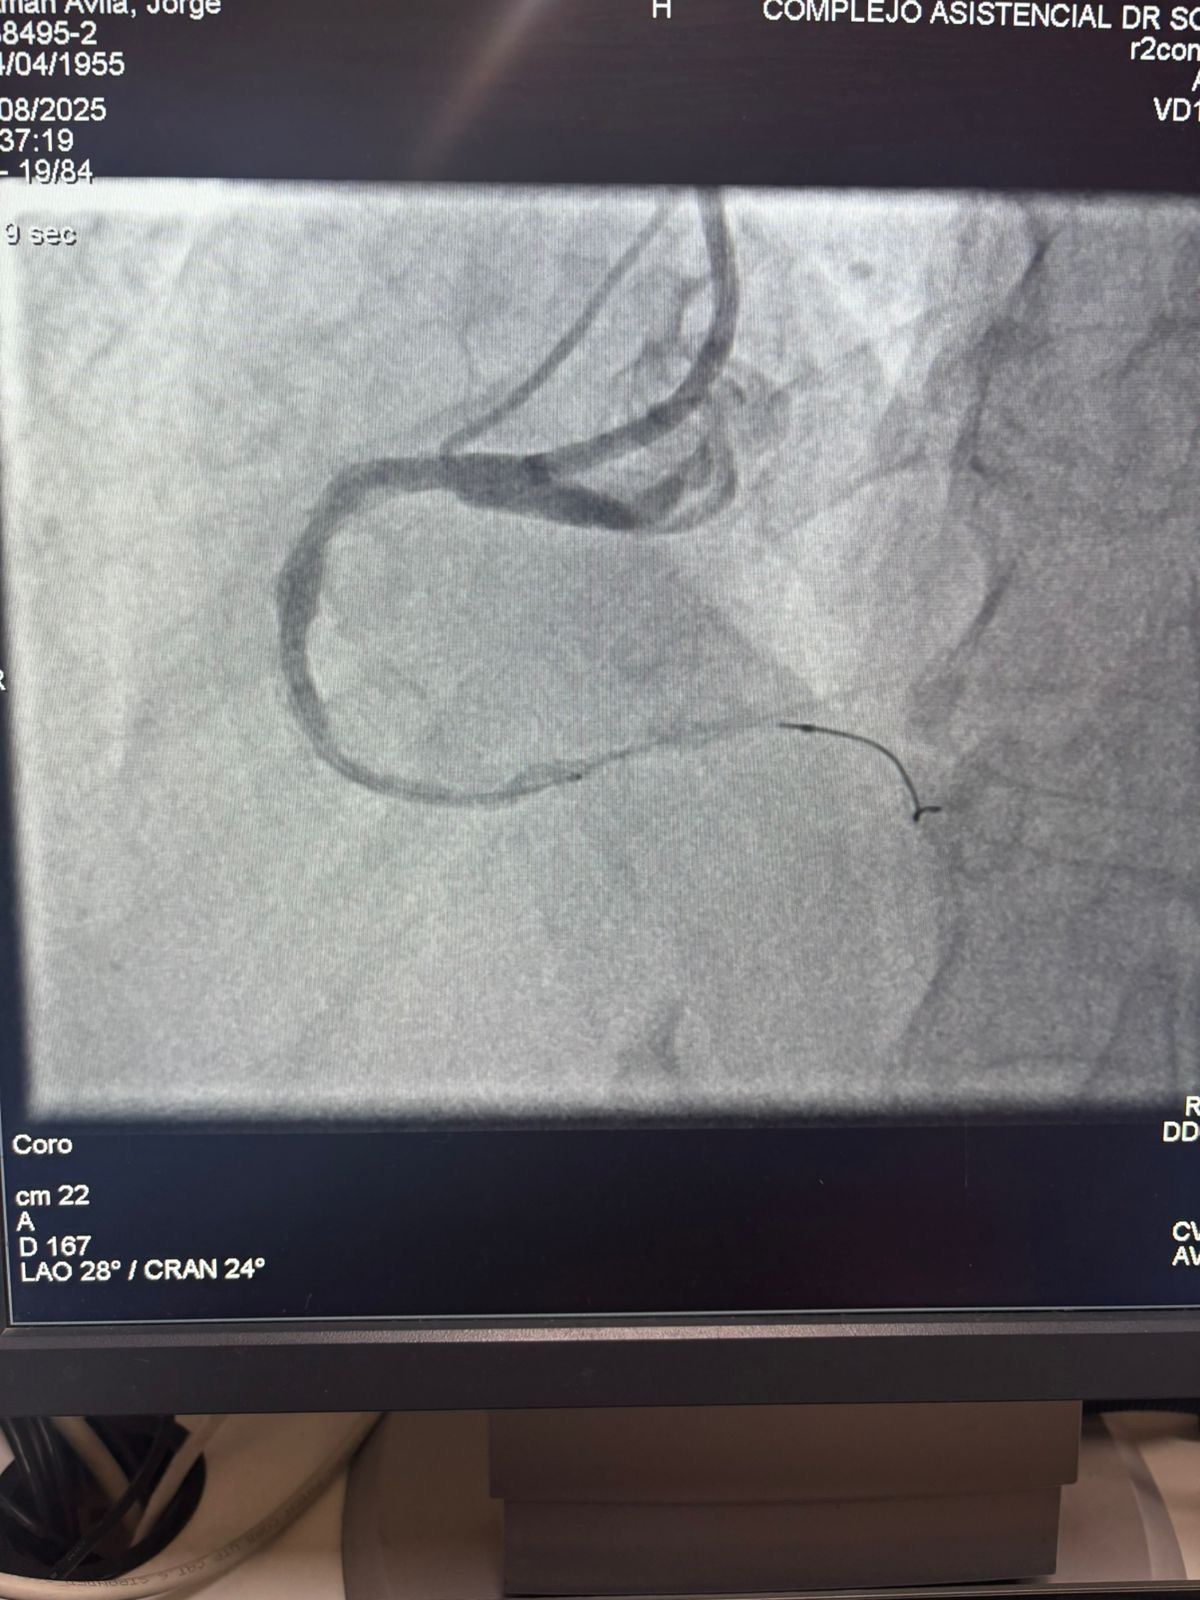

Nous sommes fiers de partager un cas remarquable de l'Hôpital Sótero del Río, Chili, où le Dr Martín Valdebenito a traité avec succès une lésion fortement calcifiée dans l'artère coronaire droite (première courbe) en utilisant notre système de cathéter de dilatation coronaire IVL Vesscrack.

La procédure a obtenu des résultats exceptionnels, avec la région calcifiée effectivement fissurée et l'écoulement du navire restauré. Cela marque une autre étape importante dans l'élargissement de l'accès mondial à des solutions avancées pour la calcification coronarienne complexe.

La comparaison entre les images angiographiques pré-procédure et post-procédure démontre clairement l'impact clinique significatif de notre technologie IVL.